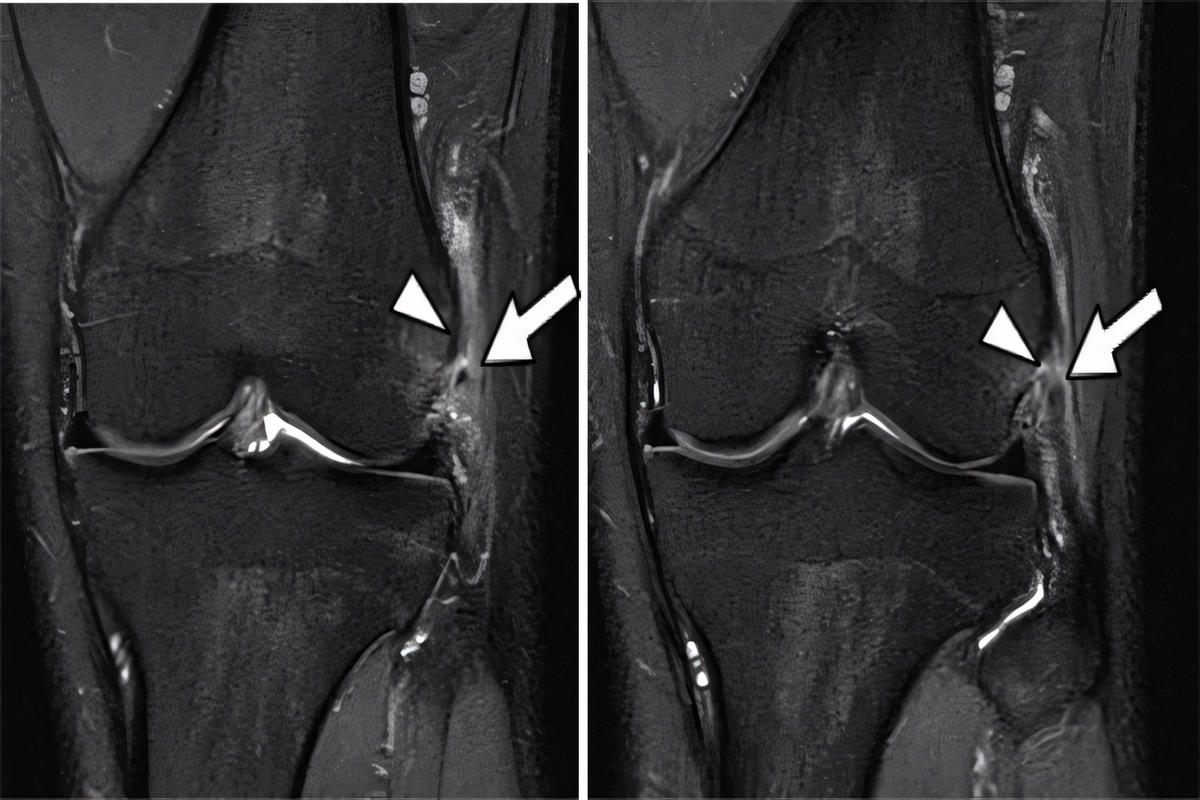

Μαγνητική τομογραφία (MRI), η οποία αποτελεί την πιο αξιόπιστη εξέταση για τον καθορισμό του βαθμού ρήξης και τον έλεγχο συνοδών κακώσεων (χιαστοί σύνδεσμοι, μηνίσκοι).